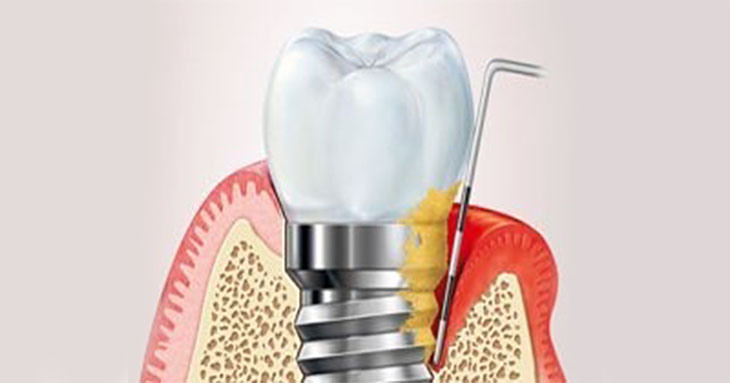

Este curso ofrece las bases biológicas para entender el porqué de la mucositis y comprender por qué 1 paciente con implante de cada 4 desarrolla Periimplantitis.Incluye los factores de riesgo y como tratarlos de forma predictiva en el tiempo.

Este curso te ayuda a comprender porque la colocación de implantes dentales son altamente predictivos, la posibidad de fracaso y sus complicaciones clínicas. La observación detenida y el diagnóstico planificado de los tejidos duros y blandos a tratar le garantiza al paciente y al profesional el éxito del tratamiento.